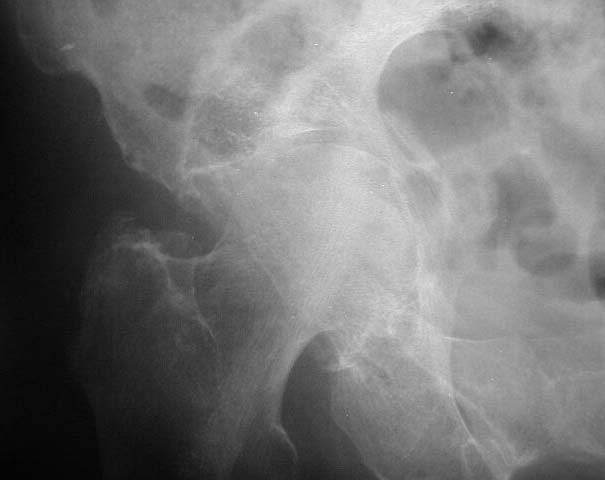

Active 91 yo female who tripped on a step and fell while working as a volunteer, sustaining fracture to the right acetabulum. She was community ambulator prior to injury. Minimal medical problems given her age -- Hypertension (well controlled), anemia, mild COPD (chronic obstructed pulmonary disease)with mild hypoxemia, history of intertrochanteric fracture left hip 1998, and inability to tolerate any oral or parenteral narcotics (nausea and vomiting even with Darvocet, even when young.)

AP1

The inlet view is perhaps the most impressive. Any insight, thoughts, personal experience(s),and/or views on management in your communities would be helpful.